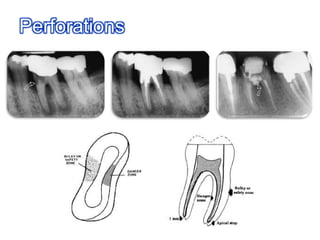

For ledges and perforations

Procedural Errors During Cleaning & Shaping